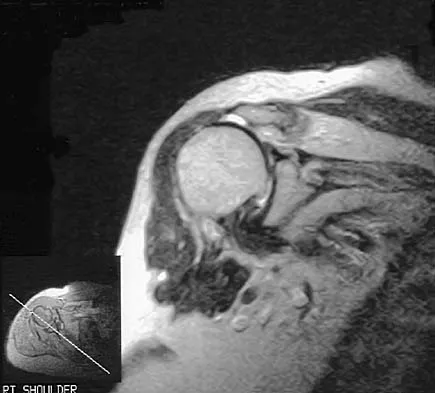

A 38-year-old left hand-dominant bodybuilder reports ecchymosis in the left axilla and anterior brachium after sustaining an injury while bench pressing 3 weeks ago. Coronal and axial MRI scans are shown in Figures 16a and 16b. What treatment method yields the best long-term results?

Explanation